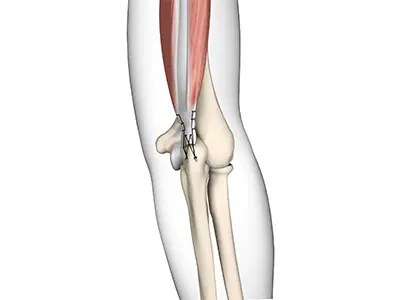

UCL Reconstruction (Tommy John Surgery)

Commonly called Tommy John surgery, this procedure involves reconstructing a damaged ligament on the inside of the elbow called the ulnar

Elbow Ligament Reconstruction

The elbow joint is supported by the ulnar collateral ligament, radial collateral ligament, and the annular ligament.

Ulnar Collateral Ligament (UCL) Injury

The ulnar collateral ligament (UCL), also called the medial collateral ligament, is located on the inside of the elbow and connects the ulna bone to the humerus bone.